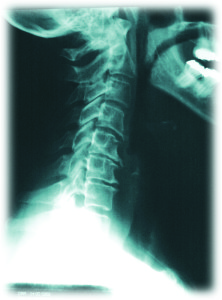

Bien des gens consultent un chiropraticien afin d’en avoir l’heure juste sur l’état de leur colonne vertébrale, dont la mobilité et l’alignement peut être affectée par l’arthrose.

- Colonne cervicale (surtout le bas du cou C5-C7 car plus de stress à ces niveaux)